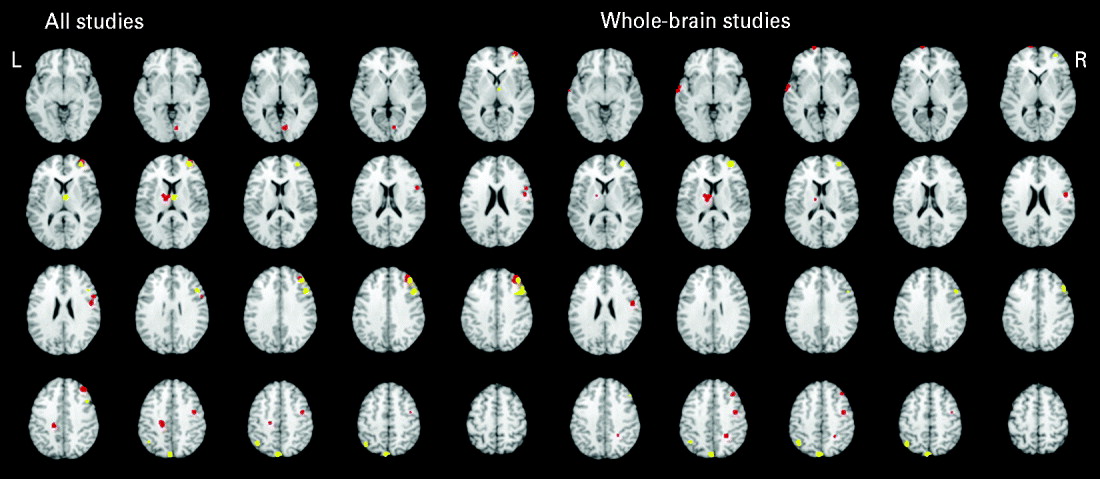

All studies

Table 3 and Fig. 2 present the significant functional activations from the 17 studies (18 samples of relatives and controls). Eight clusters were found for the controls greater than relatives contrast and six clusters were found in the relatives greater than controls contrast. In both of the contrasts, two overlapping right middle frontal regions consistently showed hypo- and hyperactivity in relatives. Table 2 provides a qualitative review of prefrontal activation patterns in individual studies and is elaborated on in the discussion to better understand the current results. Additionally, control subjects activated to a greater degree the right inferior frontal, right precentral, left posterior cingulate, left thalamus and right lingual regions compared to relatives. By contrast, relatives activated to a greater degree the right superior frontal, right thalamus, right precentral, left inferior parietal and left precuneus regions compared to controls.

Fig. 2. Above-threshold brain activations for contrasts of controls greater than relatives (red) and relatives greater than controls (yellow) for all executive functioning studies combined and whole-brain studies only. L, left; R, right.

Whole-brain studies

A separate analysis of seven whole-brain studies (eight samples) was conducted to assess the potential impact of a prior hypothesis testing used in ROI and hybrid whole-brain/ROI approaches on the meta-analysis results (Table 3, Fig. 2). Eight clusters were found for the controls greater than relatives contrast and four clusters were found for the relatives greater than controls contrast. Many commonalities were found between the two analyses. Notable differences from the all-studies analysis included the finding that the middle frontal regions solely demonstrated hyperactivity in relatives compared to controls, suggesting that inclusion of ROI and hybrid approaches biased towards finding functional activations in the middle frontal region and specifically reduced activation.

One objective of this meta-analysis was to assess the impact of using an ROI methodology on resultant functional activations. Although the pattern of results was mostly similar, one notable difference was that the middle frontal regions that demonstrated both hypo- and hyperactivity when all studies were included demonstrated solely hyperactivity when only whole-brain studies were included. This suggests that using ROIs that a priori focus on prefrontal regions might bias towards finding reduced activity in the middle frontal region. However, this finding should be interpreted with caution because of the reduced number of studies in this analysis. Although ROI analyses can overlook some regions and favor others, the ROI methodology has several strengths, including being useful for hypothesis-based testing, replications, and statistical power. To reconcile benefits with costs, future studies may consider conducting and reporting both ROI and whole-brain voxel-wise analyses.